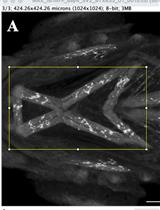

Micro-computed tomography (micro-CT) is a powerful, non-destructive imaging technique that creates high-resolution 3D images of the internal structures of small animal models such as mice and rats. Familiarizing oneself with micro-CT imaging and data analysis can be overwhelming without easy-to-follow, clear instructions. Training on new instruments is often a task exclusive to a select subset of researchers, leaving the majority of potential trainees without a technical grasp of how to navigate the instructions. This protocol on the use of micro-CT aims to bridge that gap by providing a clear, step-by-step guide to acquire and analyze micro-CT images from mice for quantitative data. By exclusively detailing the necessary procedural steps from start to finish and overcoming complex user interfaces during imaging operations and analysis, this protocol will equip new micro-CT users with the ability to measure mouse body composition (bone, body fat, and lean muscle mass) and identify and quantify lung fibrosis. This approach applies to researchers with a basic understanding of medical imaging, animal care, and software analysis.